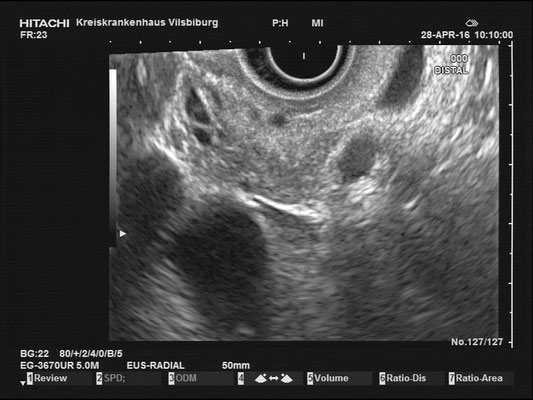

Common bile duct (CBD)

For a full examination of the common bile duct (CBD), we want have a great view of the most distal part, at the duodenal papilla. Optimally we can identify the double duct sign (or as I like to call it the "money shot") and work our way towards the liver. The CBD is joined by the hepatic artery and Portal vein, making up the Glisson's Triad. Using the doppler signal will help differentiate the vessels.

The most observant viewers will have noticed that not all images above depict normal findings but some abnormalities. (my bad ;)